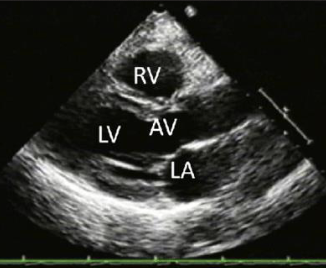

what view is this

Parasternal long axis

how is the transducer placed for parasternal long axis view

placed to left of the sternum in the 3rd, 4th, or 5th intercostal space

indicator towrds right clavicle (11’oclock)

what does plax allow you to see

everything but the right ventricle